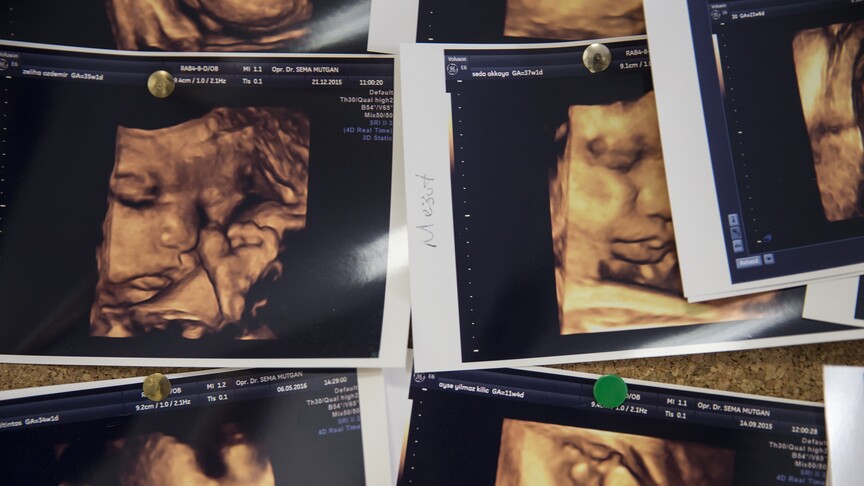

Annenin gençliğinde oluşan genetik mutasyonlar, bebeğinde hemofiliye yol açabiliyor. Yeni araştırmalar, annelerin gençlik dönemlerinde yaşadıkları genetik mutasyonların, doğacak çocuklarında hemofili gibi kanama bozukluklarına neden olabileceğini ortaya koydu. Bu durum, genetik hastalıkların ailelerde nasıl nesilden nesile geçebileceğini anlamak açısından önemli bir buluş. Annenin gençliğinde gündemindeki gelişmenin ana çerçevesi ve öne çıkan noktaları kısaca aktarılıyor. Araştırmalar, hemofili riskinin annelerin genetik geçmişiyle bağlantılı olduğunu gösteriyor. Bu bulgular, genetik danışmanlık ve tarama programlarının önemini artırıyor. Gelişmenin nedenleri ve muhtemel sonuçları öne çıkıyor. Odak başlıklar: annenin, gençliğinde, oluşan